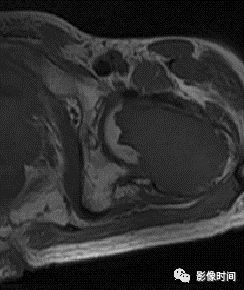

(二)瘤软骨  为肿瘤细胞产生的软骨基质,多来源于软骨类肿瘤,或内有化生瘤软骨成分的其他肿瘤如成软骨型骨肉瘤。瘤软骨为软组织密度,未钙化时,主要通过 MRI 检查显示。

由于瘤软骨多由富含水分及粘多糖的透明软骨构成,故 T1WI 呈偏低信号,T2WI 或 PDWI 呈明显高信号,被低信号的纤维间隔分开呈分叶状(图 24、图 25a-b),增强扫描多呈不均匀分隔状强化(图 25c),主要是纤维间隔强化,瘤软骨强化不明显之故。

图 24  瘤软骨:内生软骨瘤

图 25  瘤软骨:内生软骨瘤